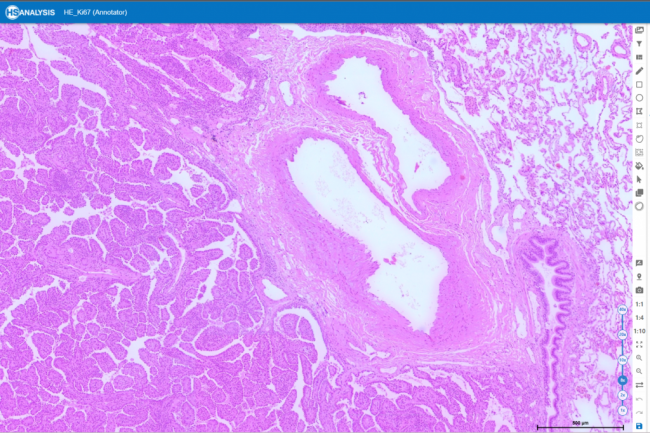

A picture of the detection of Healthy tissue and Adenoma

An example of detecting Carcinoma and Adinoma.

Zoom out view: Many healthy glands were found.

Zoom in view: Many healthy glands were found.

Zoom out view: Numerous Adenoma detected.

Zoom in view: Numerous Adenoma detected.

Zoom out view: Numerous Carcinoma detected.

Zoom in view: Numerous Carcinoma detected.

HE (Hematoxylin and Eosin) staining is a crucial histological technique in pathology. By highlighting cellular elements, it helps pathologists assess colorectal cancer using biopsy samples. The process involves staining tissue slices with Hematoxylin for nuclei and Eosin for cytoplasm and matrix, enabling the analysis of tissue properties and architecture. This aids in detecting, grading, and planning treatment for colorectal cancer patients.

Figure below displays a specific area without applying any model to it, including the “Gesund” structure.

is the same area with manual annotations specified by me. The result of HyperCrcNet (Type 1) both are the model trained with 1.6K and 4.6k GTD.